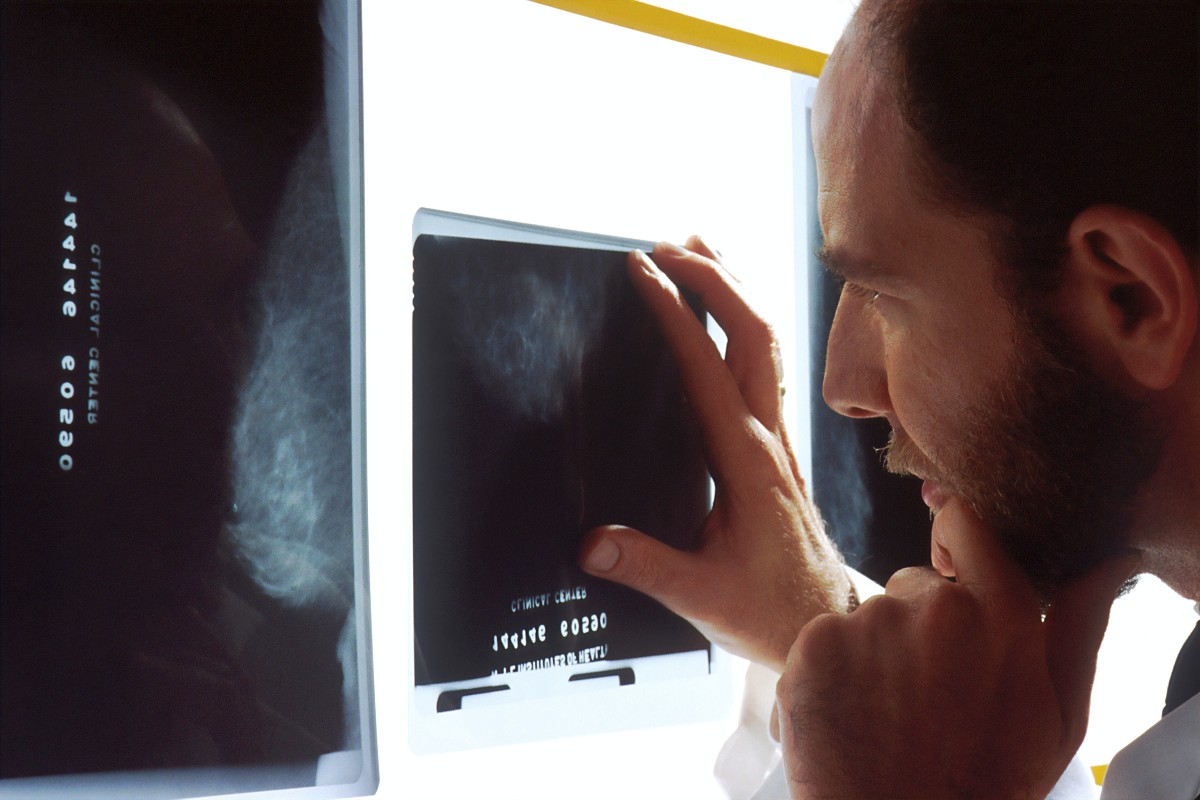

Νέα θεραπεία δίνει ελπίδα σε καρκινοπαθείς τελικού σταδίου

Μια νέα θεραπεία για τον καρκίνο μπορεί να σταματήσει την εξέλιξη της νόσου σε ασθενείς που είναι ανθεκτικοί στην ανοσοθεραπεία. Σύμφωνα με δημοσίευμα του Guardian, επιστήμονες στο Ηνωμένο Βασίλειο ανακάλυψαν μια νέα θεραπεία που δίνει ελπίδα στους καρκινοπαθείς και μπορεί να σταματήσει την εξέλιξη της νόσου. Στις έρευνες στο Ηνωμένο Βασίλειο συμμετείχαν ασθενείς με καρκίνο […]